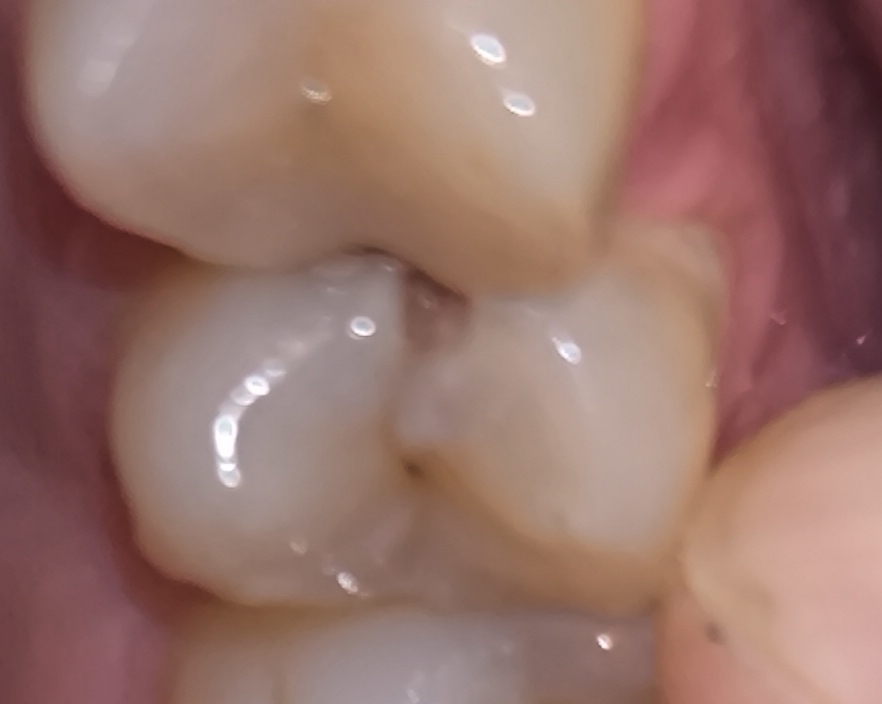

Аноним 09/09/25 Втр 12:47:10 1639465 110

Короч пролечил зуб гдет месяц назад, но он болит при накусывании.

Где-то через неделю после пролечивания ходил снова туда, мне типа врач сказал "ну кариес был глубокий нерв успокоится, попей нимесил" и отправил, зуб все еще болит, иногда чешется. Есть варик что он пройдёт или всетаки идти(явно к другом врачу) чтоб уже удалили нерв нахуй?